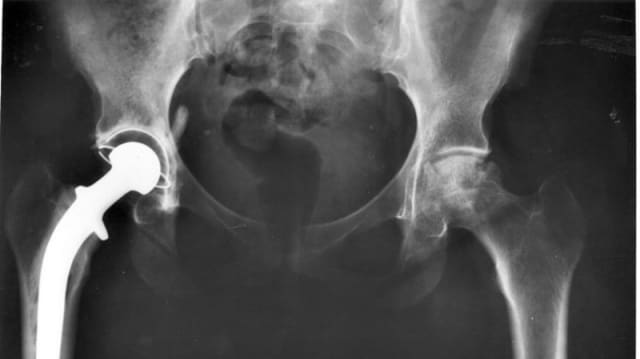

Nebst der Vergabe von Mindestfallzahlen will der Vorreiterkanton Zürich die Qualität von Spitalbehandlungen weiter ausbauen. Für ein weiteres Instrument für das Qualitätscontrolling rückt die Gesundheitsdirektion und der Fachverband Swiss Orthopaedics für die Umsetzung nun näher zusammen.

Konkret soll ab Mitte 2019 die Lebensqualität bei Patienten mit einem künstlichen Hüft- oder Kniegelenk ermittelt und dokumentiert werden. Und zwar anhand eines Fragebogens vor der Operation – und ein Jahr nach der Operation, wie der Kanton Zürich mitteilte.

Die Ergebnisse sollen mit den Revisionsraten des Implantat-Register für Hüft- und Knieimplantate abgeglichen und zuhanden der Spitäler und eines Qualitätsboards ausgewertet werden.

Ziel sei es, dass die Spitäler durch den Vergleich untereinander, der unter Aufsicht des Qualitätsboards erfolgt, ihre Indikations- und Ergebnisqualität gezielt verbessern könnten. Die Initiative zum Projekt mit Pioniercharakter hat die Gesundheitsdirektion ergriffen, wie Michael Vetter von der Abteilung Versorgungsplanung sagt.